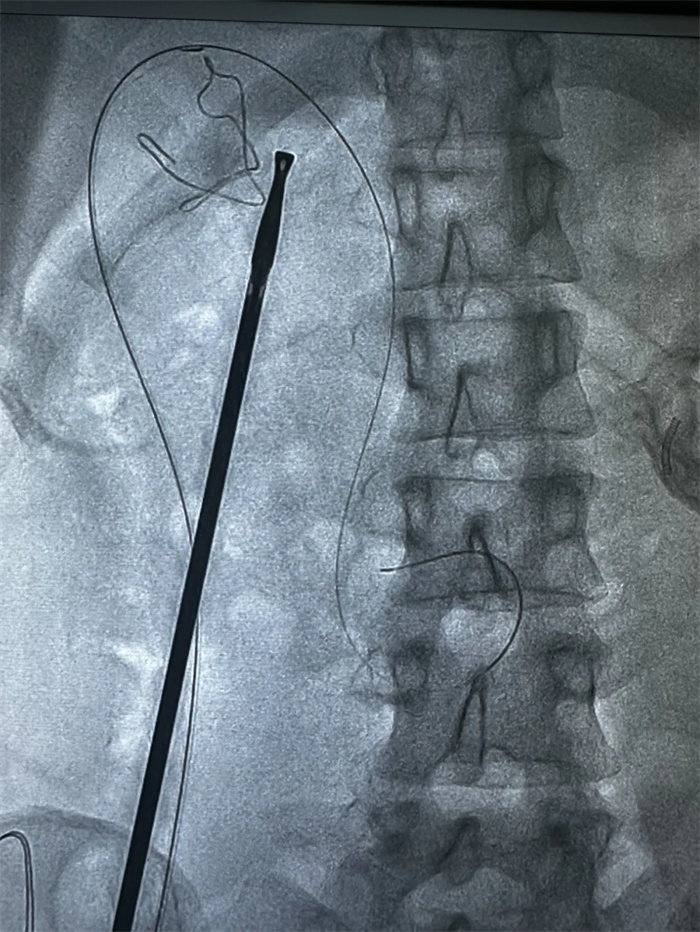

國(guó)慶節(jié)期間,西藏阜康醫(yī)院為了確保醫(yī)療服務(wù)的連續(xù)性和穩(wěn)定性,持續(xù)踐行著「無(wú)假日醫(yī)院」的服務(wù)承諾。在此期間,我院肝膽胰外科成功完成了首例同期LC(腹腔鏡下膽囊切除術(shù))+內(nèi)鏡下逆行胰膽管造影(ERCP)+oddi括約肌切開取石(EST)+鼻膽管引流術(shù)(ENBD)。

患者是一名中年女性,因右上腹疼痛1周,并且癥狀持續(xù)加重,第一時(shí)間來(lái)到西藏阜康醫(yī)院肝膽胰外科就診。入院后完善檢查,提示膽囊多發(fā)結(jié)石合并膽總管結(jié)石,膽總管內(nèi)徑11mm,肝功提示膽紅素正常、轉(zhuǎn)氨酶升高,需進(jìn)行手術(shù)治療。

手術(shù)中,榮譽(yù)院長(zhǎng)楊闖、主治醫(yī)師曹君貴首先進(jìn)行了LC術(shù),術(shù)中經(jīng)膽囊管插管后,由曹君貴主治醫(yī)師再行ERCP+EST取石+ENBD術(shù),順利解決膽總管結(jié)石。